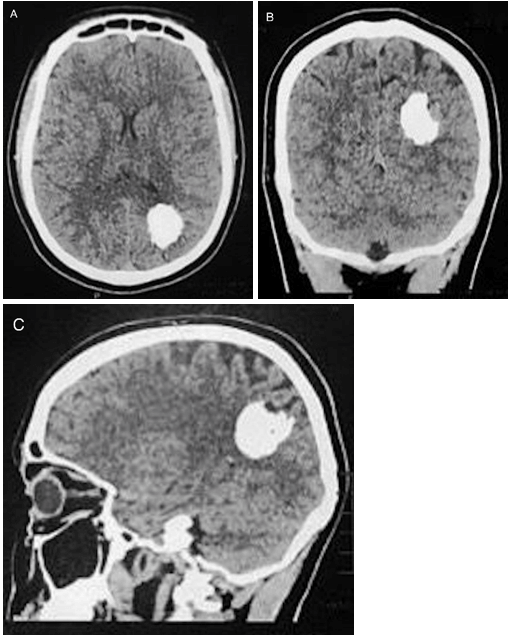

Figure 1: A-C) Preoperative non-contrast head CT showing a calcified parietal lesion.

The electroencephalogram disclosed left centrotemporal cortical epileptogenic activity. Head computed tomography (CT) showed a nodular calcified lesion, located in the left precuneus and inferior parietal lobule (Figure 1). On brain magnetic resonance (MR), there was an oval-shaped lesion measuring 2.7 x 2.4 x 1.9 cm in its largest axes, of heterogeneous intensity but with a low signal intensity predominance, mainly on the susceptibility-weighted sequences, without restricted diffusion or contrast enhancement (Figure 2). There was little adjacent edema. Considering the significance of the voluminous calcification, a screening for metabolic disturbances of some minerals was performed: calcium, magnesium, ferritin, T4 (thyroxine), TSH (thyrotrophic stimulating hormone), calcitonin, and parathormone serum levels were normal, while phosphorus and transferrin serum levels were below the normal range. Cervical ultrasound depicted a well-defined solid oval nodule, predominantly hypoechogenic, located in the left thyroidal lobe, with central and peripheral vascularization; the parathyroid regions, though, did not show any abnormalities. At this moment, the diagnostic hypotheses of cavernoma, calcified neurocysticercosis, and calcified intra-axial meningioma were proposed. A lumbar tap was then performed, and the cerebrospinal fluid analysis was completely normal, being the immunological test (ELISA) for neurocysticercosis negative.